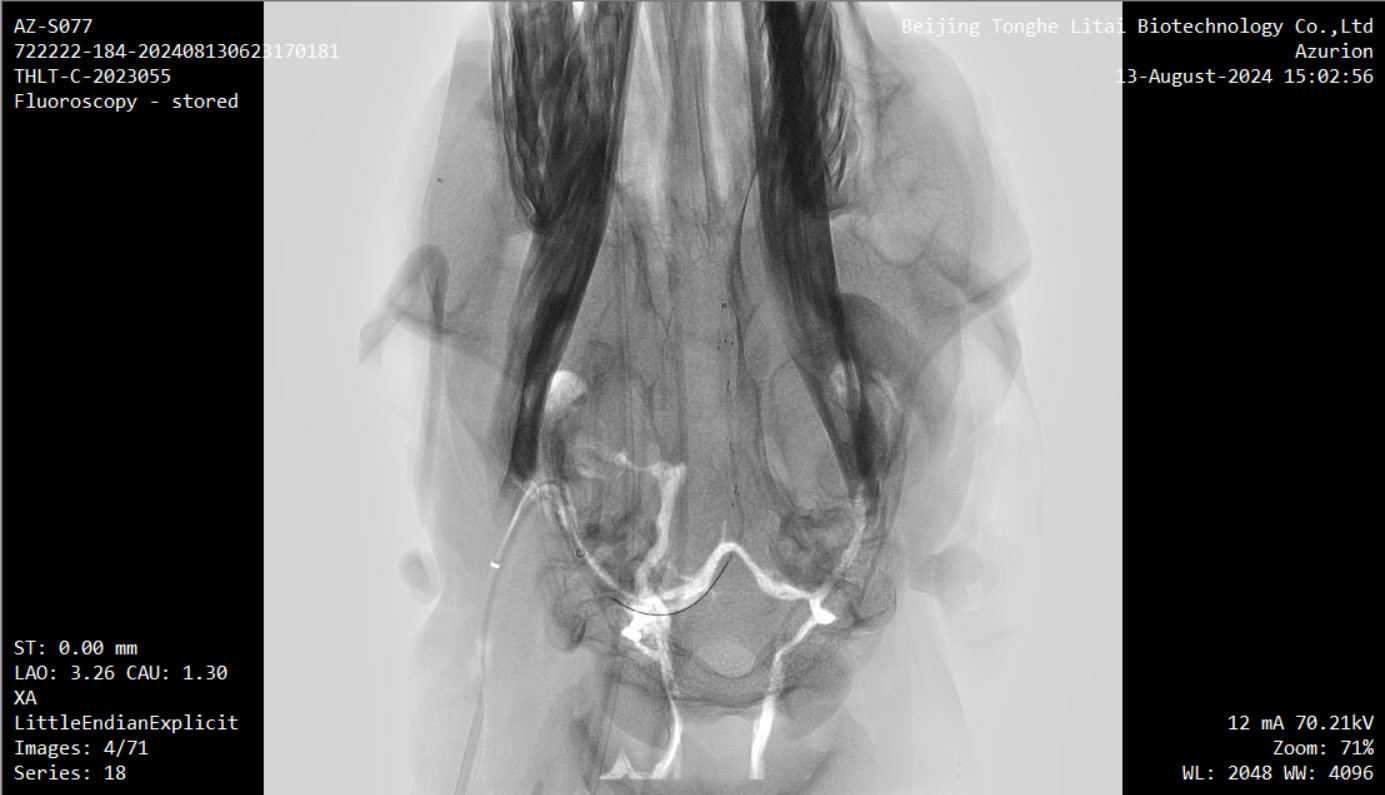

本次试验是在前期两项试验基础上取得的进一步成果,内容包括将无线传输设备植入实验动物皮下,并将采集到的介入式脑电信号通过无线传输设备传出,实现了稳定、高效的信号传输;以及通过介入手术将先前导入羊颅内血管壁上的介入式脑机接口传感器安全取出,整个过程在DSA造影引导下进行,确保了手术过程的安全性。